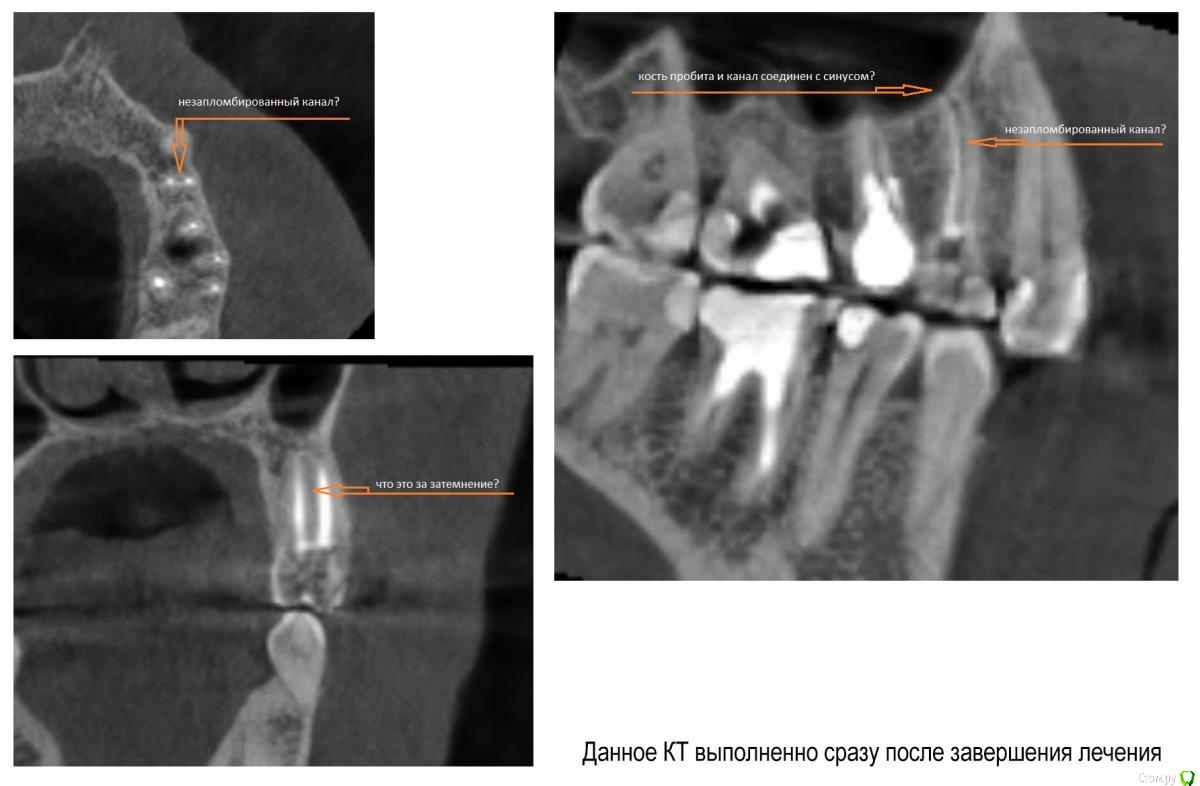

andreymir Опубликовано 7 марта, 2021 Поделиться Опубликовано 7 марта, 2021 Было проведено лечение каналов из-за кисты на 24 зубе. 2 канала, 2 корня. На КТ каналы запломбированы, но между каналами на всем протяжении каналов прослеживается затемнение. В описании, ранее сделанного КТ (в процессе лечения) рентгенологом указано, что корни срослись (каналы?) на всем протяжении. Затемнение между каналами на всем протяжении зуба на ранее сделанном КТ, к которому было приложено данное описание, не прослеживается. Это затемнение обнаруживается только на КТ, выполненном сразу после лечения. Затемнение между каналами на последнем КТ выходит за границу зуба, за границу кости и сливается с синусом. Скрины с КТ прилагаю к данному сообщению.Вопросы:1. Что это за затемнение? Не мог же появится новый канал в процессе лечения? Или это не заполненная пломбировочным материалом часть канала? Или это полость, которая соединяет каналы на всем протяжении?2. Верно ли, что раз затемнение выходит за границу зуба, то это означает, что стоматолог "перестарался", проткнул кость и провалился в синус? И теперь через весь зуб проходит не заполненный пломбировочным материалом канал связанный с синусом?3. Что делать с таким зубом? Можно ли ставить коронку, его нужно перелечить или он безнадежен и его пора менять на имплант?Спасибо!КТ ниже выполнено сразу после ЗАВЕРШЕНИЯ леченияКТ ниже выполнено в ПРОЦЕССЕ леченияЕсть КТ до начала лечения, если необходимо могу приложить в следующем сообщенииХорошего дня! Ссылка на комментарий

andreymir Опубликовано 7 марта, 2021 Автор Поделиться Опубликовано 7 марта, 2021 (изменено) у вас все нормально, не ищите проблем там где их нет. Зуб восстанавливайте искусственной коронкойБольшое спасибо вам за ответ, но я был бы вдвойне признателен за более обстоятельный ответ. Меня слегка тревожит первое изображение. Можете уточнить, что за затемнение проходит через весь зуб между двумя каналами на первом изображении и выходит в синус? Спасибо! Изменено 7 марта, 2021 пользователем andreymir Ссылка на комментарий